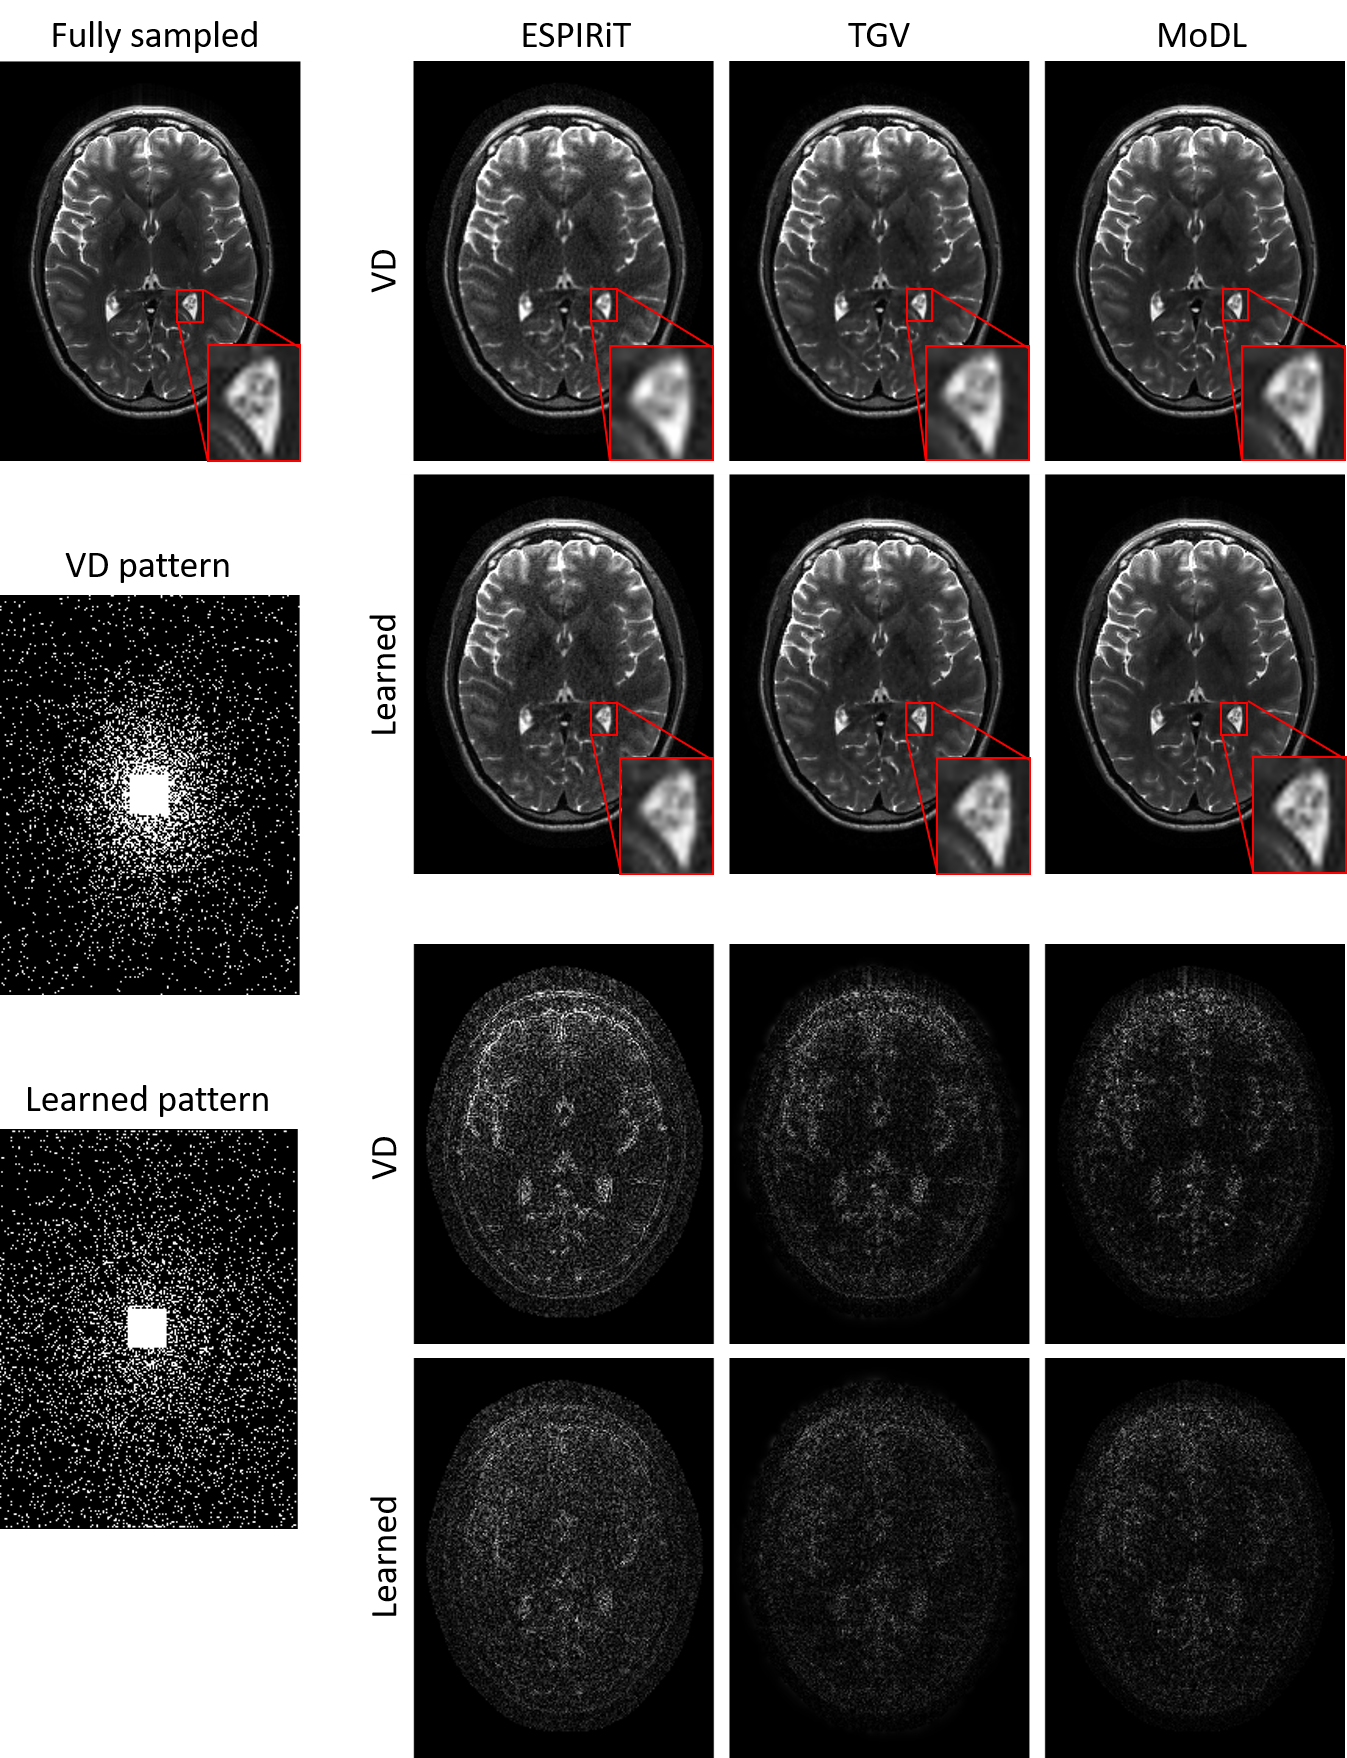

Refer to caption

Figure 3: Reconstruction results on another test slice using VD and learned sampling patterns with three different reconstruction methods. First two rows: reconstruction results; last two rows: corresponding 5×\times absolute error maps (window level:[0, 0.5]). For each reconstruction method, the learned sampling pattern produced lower global errors and sharper structural details than VD sampling pattern.

3.3 Comparison with other pattern

To compare the learned sampling pattern (’learned pattern’ in Fig. 3, generated from MoDL + BS in section 3.2) with the manually designed one with 10 % ratio, a variable density (VD) sampling pattern following a probabilistic density function whose formula is a polynomial of the radius in k-space with tunable parameters [26] was generated (’VD pattern’ in Fig. 3). ESPIRiT [25] and TGV [17] as two representative iterative methods for solving PI CS-MRI were also deployed using both sampling patterns, and the corresponding reconstruction results are shown in Fig. 3. For each reconstruction method, the learned sampling pattern captured better image depictions with lower global errors than VD pattern and the structural details as zoomed in were also sharper with the learned sampling pattern. PSNR and SSIM in Table 2 shows consistently improved performance of the learned sampling pattern over the VD pattern for each reconstruction method.